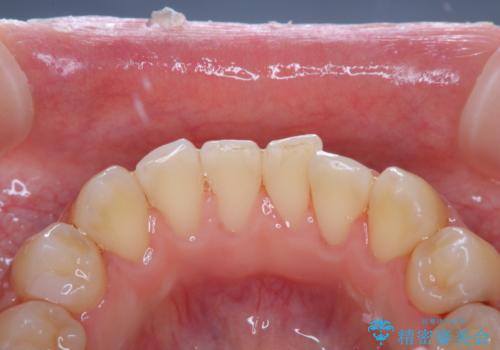

染め出しをしてのブラッシング指導とPMTCを行いました。

染め出し液を使ってプラークを染め出すことにより、普段の歯みがきで磨き残している場所を目で確かめることができます。

日々の歯磨きを上達するには、まずどこが磨けていないか認識することが大切です。